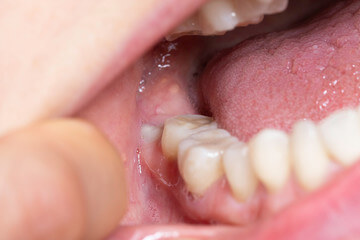

사랑니는 다른 치아에 비해 크기와 모양이 매우 다양합니다. 사랑니는 똑바로 나오지 않고 기울어져 있거나 누워있는 경우 잇몸에 묻혀 있는 부분이 많습니다.

이 때문에 음식물 찌꺼기가 잇몸과 사랑니 사이에 끼기 쉽고 칫솔이 사랑니에 잘 닿지 않아 썩는 경우가 많고 제대로 청소하지 않으면 세균이 번식하고 염증이 생기기 쉬운 상태가 됩니다.

잇몸이 부어 오르거나 아플 때 감염이 느껴지고 위턱에 있는 사랑니가 부은 잇몸을 씹으면 더 불편 해집니다. 충치는 사랑니와 사랑니 앞 치아의 뒷면에도 형성될 수 있습니다. 이러한 충치는 종종 과소 검사되며 치통이 있을 때 가장 자주 발견됩니다. 심하면 양쪽 치아를 모두 뽑아야 하는 경우도 있습니다.